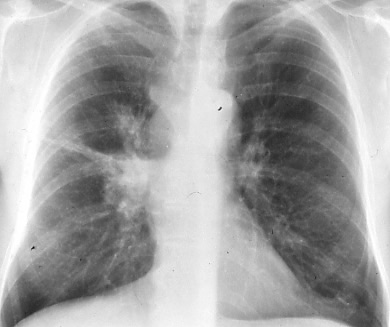

Fig. 3: Posterior-anterior radiographs showing (a) an extensive bronchogenic carcinoma in the right lung and (b) four months after initiation of chemotherapy, a complete remission, rT0.